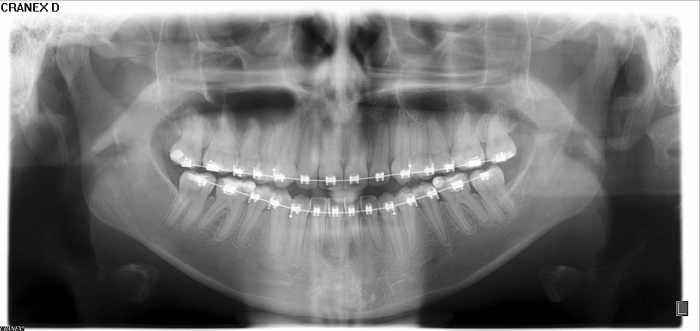

Rx panorâmico inicial